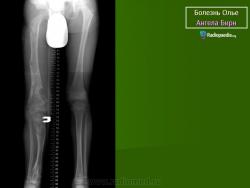

ОЛЛЬЕ СИНДРОМ (описан французским хирургом L. Ollier, 1830–1900; синоним – энхондроматоз, остеохондроматоз) – системное нарушение развития скелета, при котором на ранних этапах эмбриогенеза нарушается трансформация хряща в костную ткань; в растущей кости сохраняются очаги необызвествленной хрящевой ткани, что приводит к деформации и укорочению костей. Возможно поражение 1 (монооссальная форма заболевания), 2–3 (олигооссальная форма заболевания), 4 и более (полиоссальная форма заболевания) костей; поражаются преимущественно метафизы длинных трубчатых костей, фаланги пальцев, тазовые кости. Проявления заболевания возникают в возрасте 2–10 лет и зависят от локализации и тяжести процесса. Изменения обычно двусторонние, но асимметричные. При локализации процесса в нижних конечностях наблюдаются хромота, перекос таза, вальгусная или варусная деформация и прогрессирующее укорочение ног. При поражении верхних конечностей характерны лучевая или локтевая косорукость, выраженная деформация пальцев. Возможны патологические переломы. Нередко наблюдается малигнизация с развитием хондросаркомы. В редких случаях сочетается с гемангиомами мягких тканей (синдром Мафуччи). Диагноз уточняют при рентгенологическом исследовании, выявляющем четкие очаги овального или веерообразного просветления в метафизах длинных трубчатых костей. Тип наследования – предположительно аутосомно-доминантный. Лечение: выравнивание длины нижних конечностей с помощью ортопедической обуви, в случае выраженных деформаций показана хирургическая коррекция.

Клиническая картина. Заболевание выявляется в раннем детском возрасте, с началом ходьбы появляются деформации костей, хромота, прогрессирующее укорочение конечностей. Нередко первым проявлением болезни служат патологические переломы измененной кости; гемангиомы (при синдроме Мафуччи).Рентгенологически трубчатые кости умеренно или значительно укорочены, эпиметафизы булавовидно расширены, вздуты; в метафизах определяются очаги просветления неоднородной структуры.

Болезнь Олье.

Клиническая картина. Заболевание выявляется в раннем детском возрасте, с началом ходьбы появляются деформации костей, хромота, прогрессирующее укорочение конечностей. Нередко первым проявлением болезни служат патологические переломы измененной кости; гемангиомы (при синдроме Мафуччи). Рентгенологически трубчатые кости умеренно или значительно укорочены, эпиметафизы булавовидно расширены, вздуты; в метафизах определяются очаги просветления неоднородной структуры.